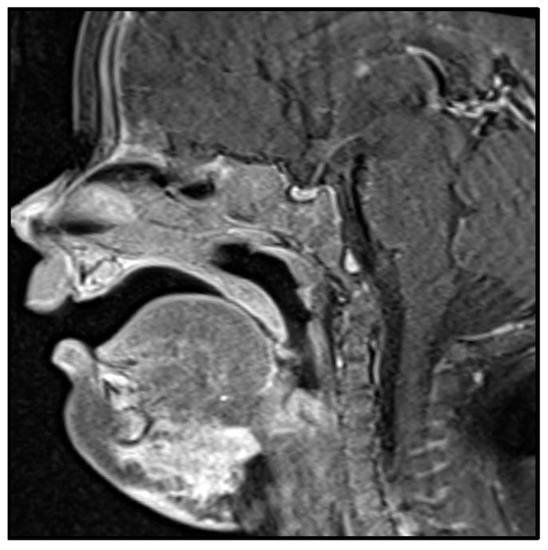

3.5.3. Clinical Presentation

3.5.4. Histologic Features